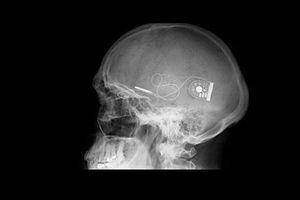

C'est l'entreprise allemande, Retina Implant, qui est à l'origine de cette technologie. Il s'agit d'une micropuce placée sous la retine, mesurant 3 mm de côté. Elle est composée de 1 520 électrodes qui captent la lumière pour la transformer en un signal électrique et le transmettre, via le nerf optique, au cerveau afin de recréer une image. Le système placé derrière l'oreille, est relié à l'implant grâce à un fil très fin qui traverse la paroi de l'oeil.